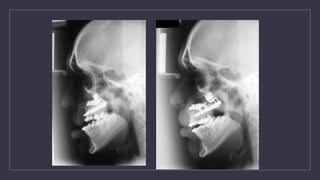

Orthognathic Surgery

• Midfacial Advancement

• LeForte osteotomies

• leave vascular pedicle attached in back

Schedule of Treatment Birth: Initial Assessment  Pre-surgical assessment 3 Month:  Primary Lip repair 9-18 month:  Palate Repair 2 Year:  Speech assessment 3-5 Year:  Lip Revision Surgery 8-9 Year:  Initial interventional Orthodontics  Preparation for alveolar bone grafting 10 Year:  Alveolar Bone Grafts 12-14 Year:  Definite Orthodontics 16 Year:  Nasal Revision Surgery 17-20 Year:  Orthognathic Surgery

Orthognathic Surgery • MidfacialAdvancement • LeForte osteotomies • leave vascular pedicle attached in back of maxilla - prevents necrosis